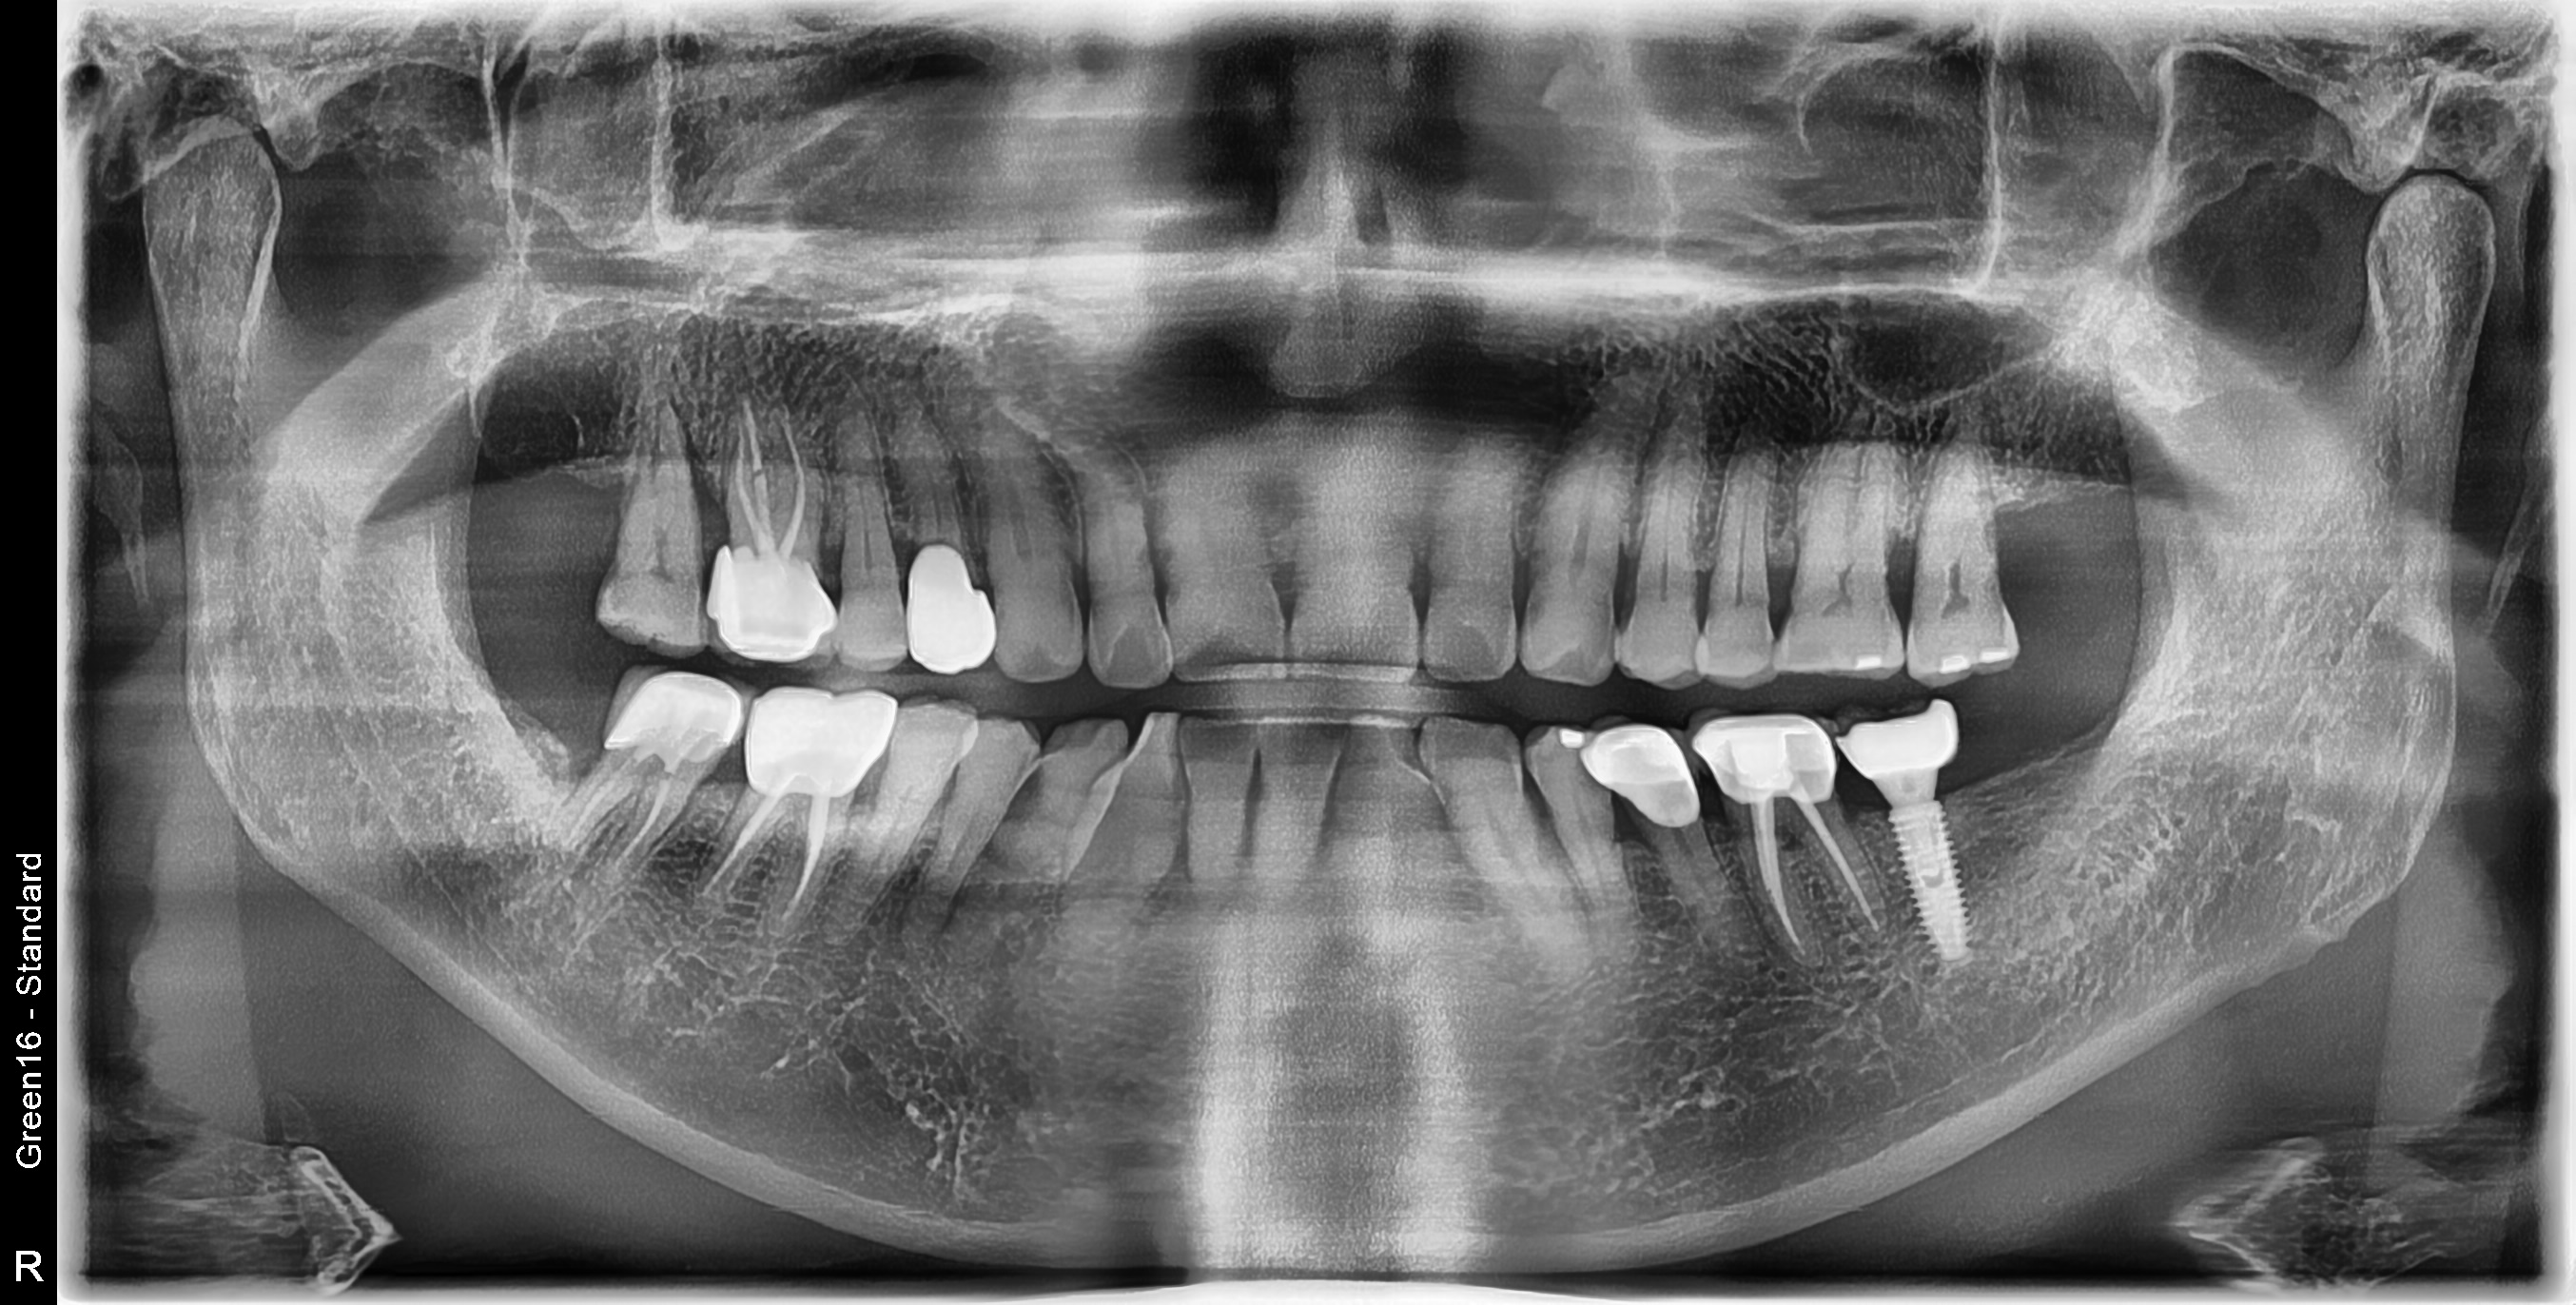

수술 전

수술 후

좌측 임플란트 흔들림 재수술 사례

전후사진